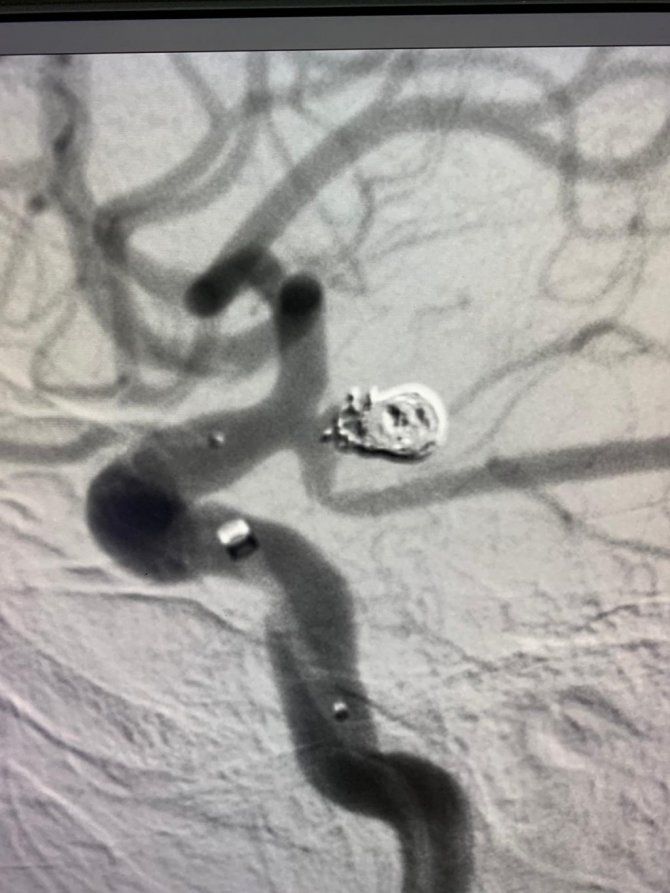

Karadeniz Bölgesi'nde ilk kez bir hastanın kasık bölgesindeki atar damarına girilerek, beyin damarlarına ulaşılabilen "Nöroendovasküler Girişim" ve Endoskopik Hipofiz Cerrahisi yöntemi uygulandı. Kanuni Eğitim ve Araştırma Hastanesi'nde Uzm. Dr. Mehmet Selim Gel ve Uzm. Dr. İskender Samet Daltaban tarafından uygulanan ve hibrit cerrahi olarak adlandırılan yöntem sayesinde bir hasta tekrar sağlığına kavuştu. Yapılan ameliyat ile ilgili bilgiler veren Uzm. Dr. Mehmet Selim Gel, "Nöroendovasküler girişim yöntemi kapalı bir şekilde hastanın kasık bölgesindeki atar damara girilerek çeşitli kateter ve teller yardımıyla beyin damarlarına ulaşabildiğimiz yöntemdir. Bu yöntem beyin damar hastalıklarının tanısı ve tedavisinde açık cerrahiye alternatif bir yöntem olmasının yanında beyin tümör hastalıklarının tedavisinde yardımcı bir tedavi yöntemi olarak da kullanılmaktadır. Beyin baloncuklarının tedavisi beyinde bulunan damar yumakları ve atardamar ile toplar damar arasındaki kontrolsüz geçişlerin tedavisi başlıca kullanıldıkları alanlardır. Trabzon Kanuni Eğitim Araştırma Hastanesi beyin cerrahi bölümünde kullanmaya başladığımız bu yöntem ile beyin baloncuklarının tedavisi beyinde bulunan damar yumakları ve atardamar ile toplar damar arasındaki kontrolsüz geçişlerin tedavisi sadece açık cerrahi olarak değil kapalı yöntemle de tedavi edilebilmektedir. Hibrit cerrahi olarak adlandırılan bu yöntem Karadeniz bölgesinde ilk kez hastanemizde uygulanmaya başlamıştır" dedi.